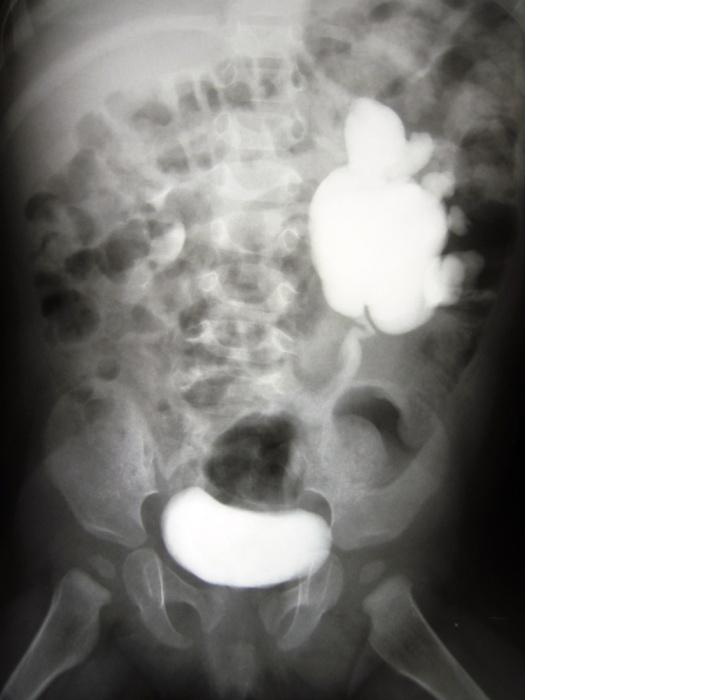

Pytanie 11

U 6-miesięcznej hipotroficznej dziewczynki podczas rutynowej kontroli pediatra stwierdził nadmierne uwypuklenie powłok w okolicy lewego nadbrzusza. Z podejrzeniem guza skierował dziecko do oddziału chirurgii dziecięcej, gdzie wykonano badania obrazowe, wśród nich urografię. Zdjęcie urograficzne wykazało, że jest to: